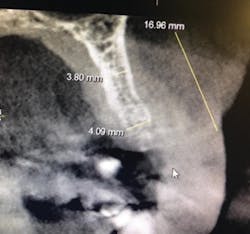

Figure 1b: Pre-op CT scan

A 50-year-old female presented with a missing tooth No. 12 that was extracted for unknown reasons more than 10 years ago (figure 7). The patient was referred to our office for an implant consultation. Upon review of a CT scan, it was revealed that at the widest area buccal-lingually there was 4.09 mm and at the narrowest 3.8 mm (figure 8). She was presented with two treatment options: bone grafting or a narrow-diameter implant. She opted for the narrow-diameter implant, as it eased several of her concerns: she was unhappy with a removable appliance, worried about a block graft for a single tooth, and finances were a burden.

Figure 8: Pre-op CT scan